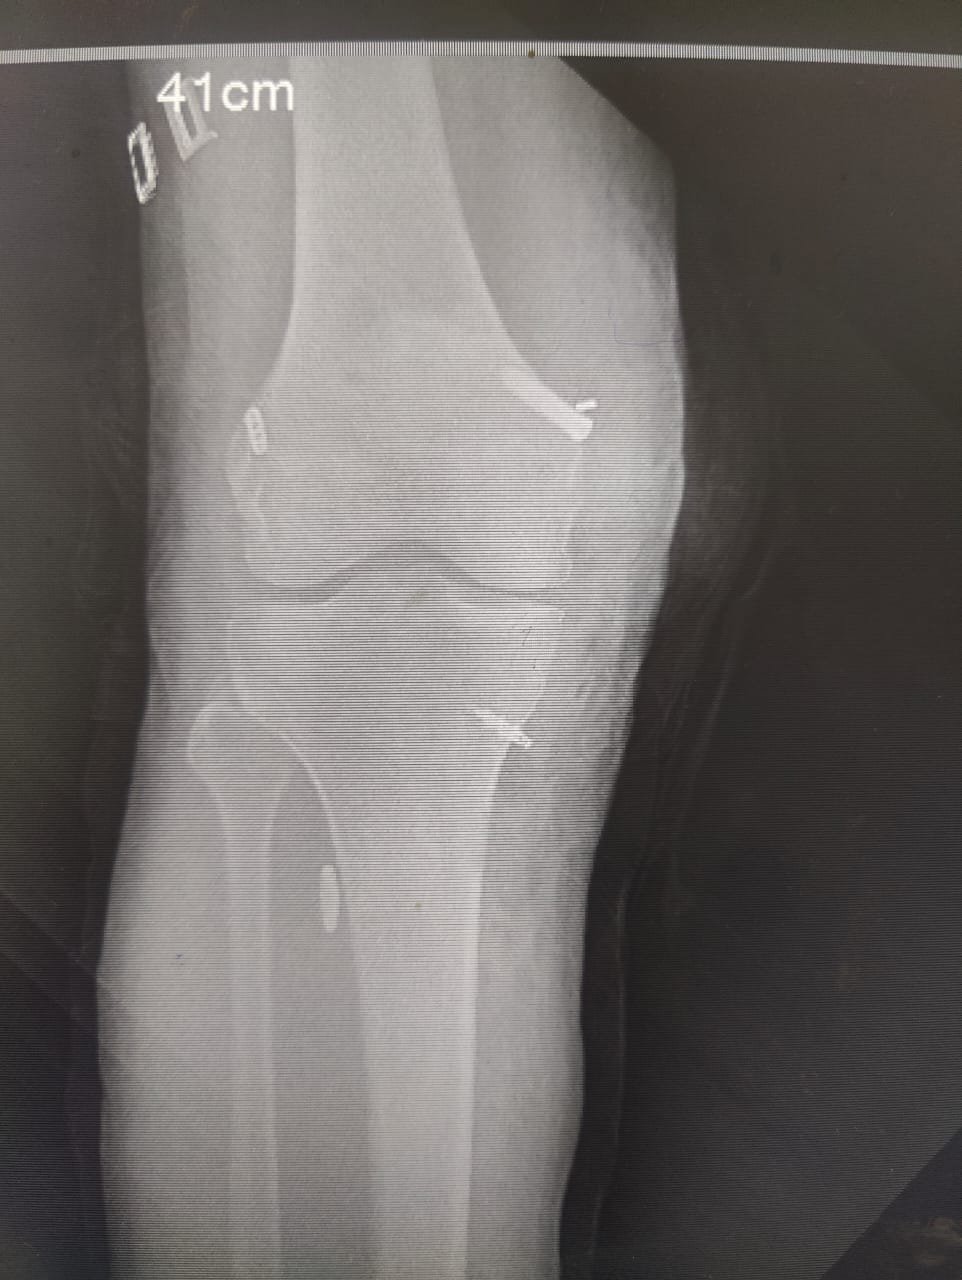

Orthopaedic Surgeon | Arthroscopy & Joint Replacement Specialist

Dr. Aditya Tripathi is a dedicated and skilled Orthopaedic Surgeon specializing in sports injuries, arthroscopy, and joint care. Known for his clinical precision, ethical practice, and patient-first approach, he focuses on helping patients regain mobility, strength, and confidence through evidence-based orthopaedic treatment. His academic background and hands-on clinical training reflect a strong foundation and a commitment to excellence in orthopaedic care.

Dr. Aditya Tripathi is widely appreciated by patients for his clear communication, honest medical guidance, and personalized treatment approach. His expertise in managing ACL tears, ligament injuries, shoulder conditions, and sports-related injuries makes him a trusted choice for comprehensive orthopaedic and sports injury care. Patients value his attention to detail, compassionate care, and focus on long-term recovery—establishing him as a reliable and respected orthopaedic specialist.

Specialization And Expertise

- ACL Reconstruction

- PCL Reconstruction

- Meniscus Repair

- Arthroscopy-Knee